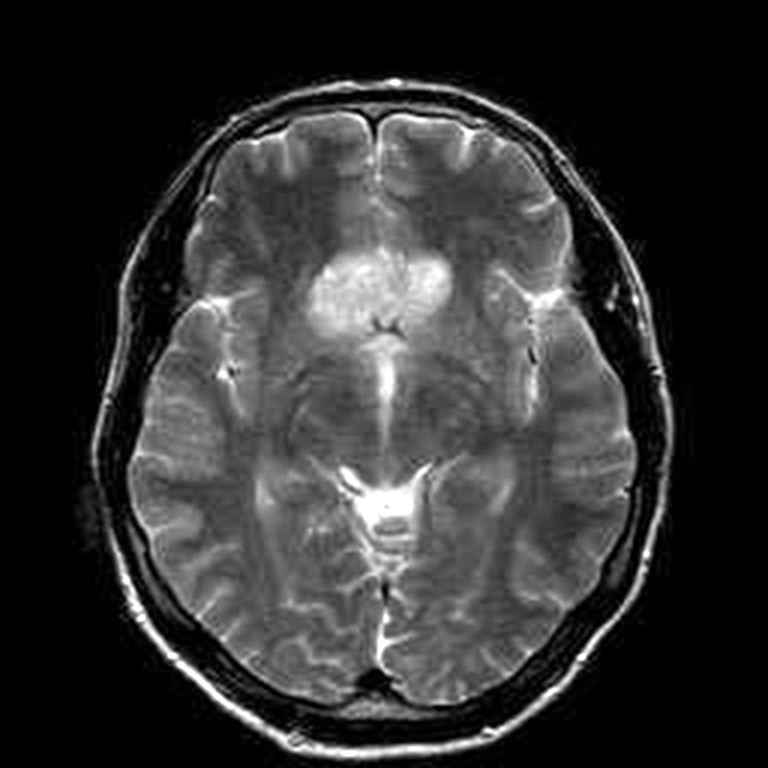

Fig. 2. Patient P., 64 years old, HIPA with suprasellar extension, central chiasmal position. Brain MRI: A – coronal projection; B – sagittal projection

A B